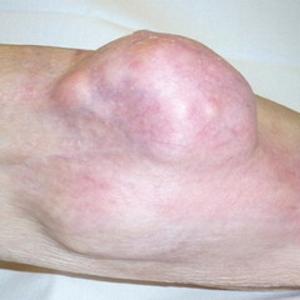

Врачи отмечают, что саркома колена может проявляться различными симптомами, которые важно распознать на ранних стадиях. К основным признакам относятся боль в области колена, отечность, ограничение подвижности и изменение формы сустава. В некоторых случаях пациенты могут заметить образование опухоли, которое становится заметным при физическом осмотре.

На ранних стадиях заболевания явные признаки опухоли в колене могут отсутствовать. Это часто приводит к тому, что саркома выявляется только после появления метастазов, которые распространяются через лимфатическую и кровеносную системы в удаленные органы. С прогрессированием опухоли страдают сухожилия, кости, хрящи и другие компоненты сустава. В процессе развития саркомы колена могут проявляться следующие симптомы:

- отечность в области колена;

- отек тканей вокруг сустава.

Со временем кожа вокруг сустава может темнеть. Поскольку структуры сочленения разрушаются, сустав теряет подвижность, и пациент не может наступать на пораженную ногу. На фоне прогрессирования заболевания могут возникать признаки общей интоксикации, такие как:

Увеличивающаяся опухоль может нарушать функционирование крупных кровеносных сосудов в области коленного сустава, что приводит к сильному отеку мягких тканей ниже колена и образованию участков некроза. На поздних стадиях саркома прорастает в соседние ткани, включая мышцы и костномозговой канал. Метастазы могут обнаруживаться в почках, печени, мозге и других органах.

О том, что в области коленного сустава есть злокачественная опухоль, могут свидетельствовать следующие симптомы: боль вокруг колена, которая усиливается по ночам, во время физических нагрузок, приводит к хромоте, отек, опухолевидное образование, которое заметно внешне, определяется на ощупь, увеличивается со временем.